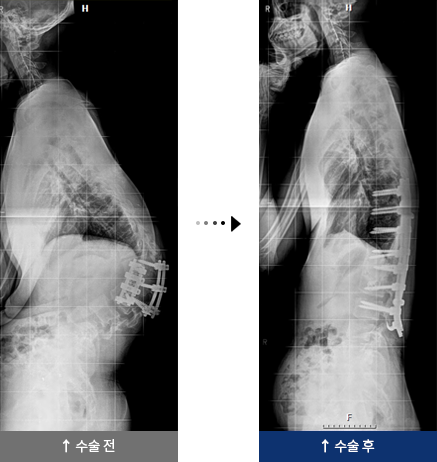

강직성 척추염